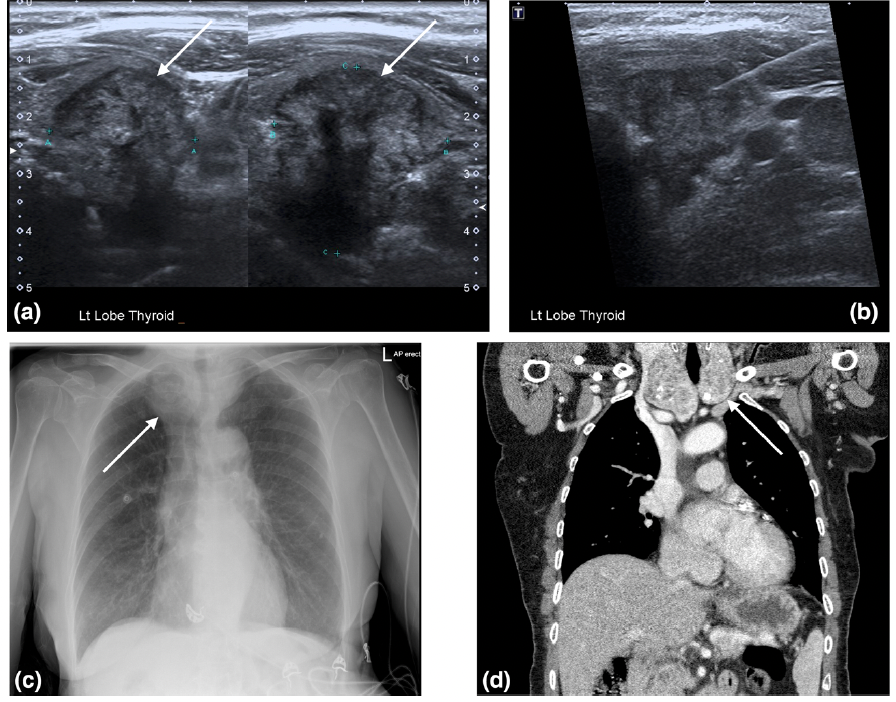

What is your diagnosis?